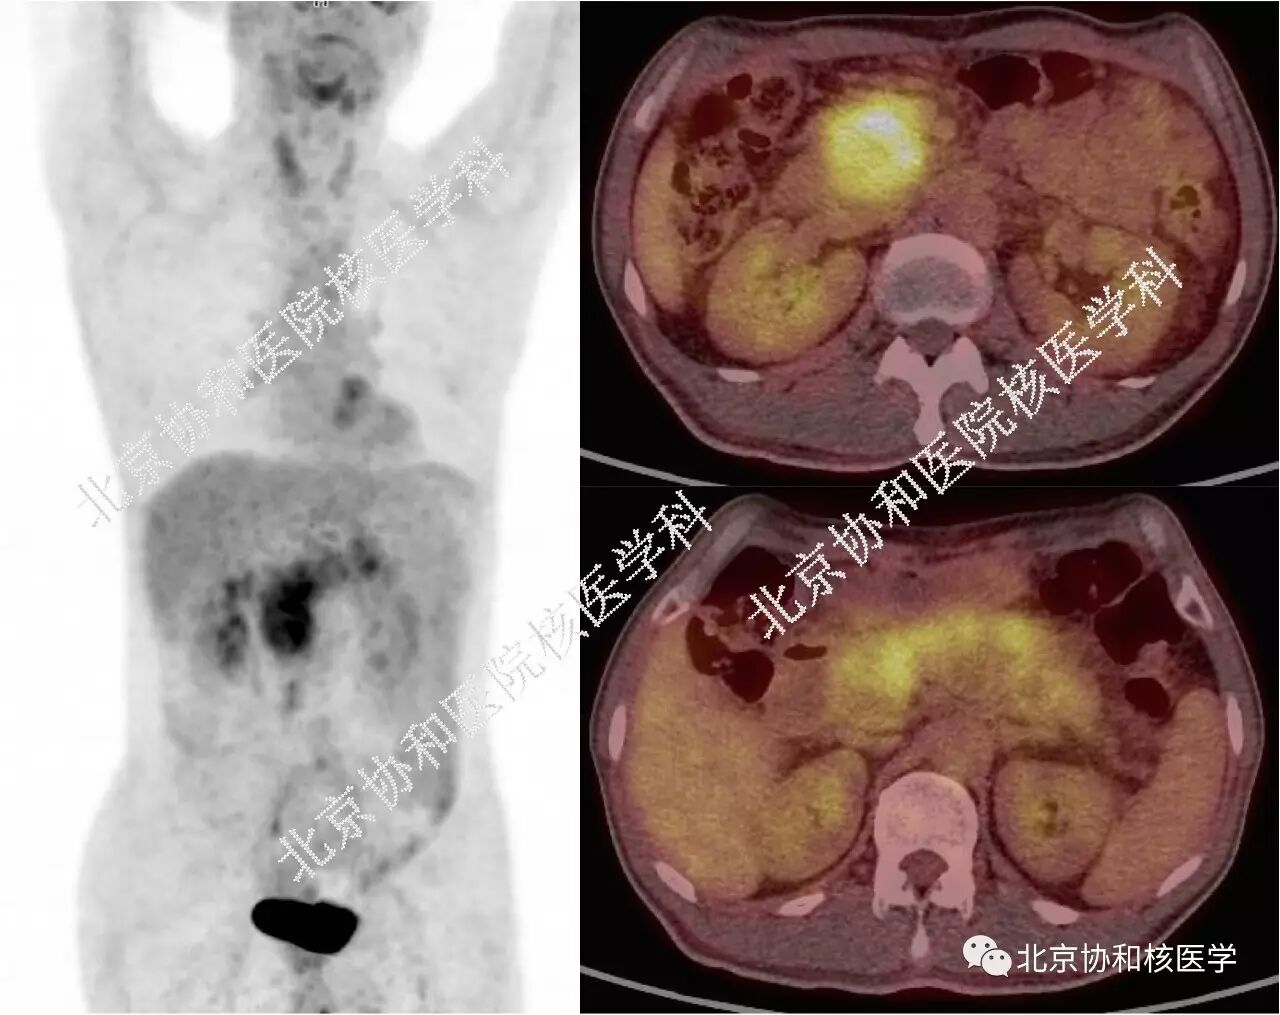

• 病例2: 中年男性,上腹痛1年余,PET/CT也见胰腺弥漫增粗,代谢不均匀增高,胰腺头颈部代谢增高较体尾部明显,增强CT见胰腺边界清晰,胰头周围见环形低强化区,体尾部见多处囊性变。

胰腺肿瘤表现为弥漫性代谢增高的情况并不多,主要考虑2种:一是tumor-induced pancreatitis,即胰腺头颈部肿瘤因阻塞胰管等原因引起远端胰腺组织急慢性炎症,这种情况相对更多见,在第13期病例中也有详细讨论(请继续戳:IgG4相关性疾病的原点),结合增强CTMR看胰头颈部有没有占位比较容易诊断。本期病例2中虽然也是胰腺弥漫性受累,但胰腺头颈部代谢比体尾部更高,恶性病变中需要鉴别的就是这种情况。这时我们需要考虑的是,若胰头部代谢更高区是肿瘤病灶,那么瘤体已经很大,临床和影像上尚未有胆道梗阻的表现,较为可疑;增强CT上胰头周围有环形低强化区,对临近血管也无侵犯、包绕,缺乏典型的胰腺癌特征。

病例2中患者行超声内镜见胰腺体、尾部呈包鞘状,见多发囊性占位,胰头及钩突显著增大,胰腺实质回声减低,胆管壁明显增厚呈三明治征,穿刺活检未见瘤细胞;血清IgG43倍升高。临床考虑IgG4相关性自身免疫性胰腺炎,予泼尼松治疗4月后复查腹部CT胰腺形态恢复正常。